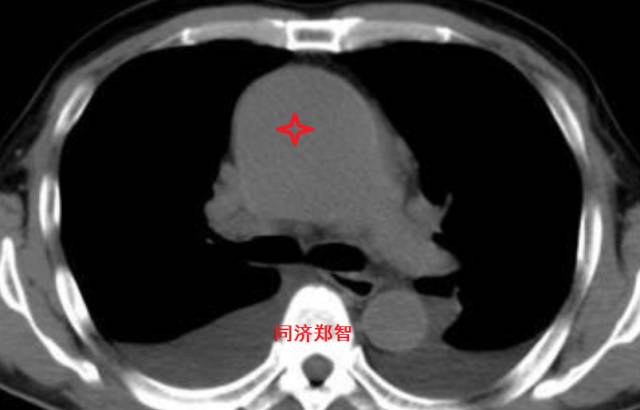

病例二

胸部平扫CT提示升主动脉增宽(红色星形标记),CTA证实A型主动脉夹层伴升主动脉夹层动脉瘤形成。